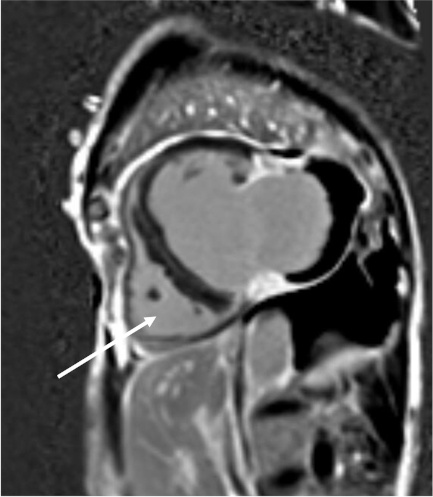

He underwent a right and left heart catheterization, which demonstrated 70% stenosis of his first diagonal vessel, 90% stenosis of his second diagonal vessel, and a second marginal artery, which was fully occluded at its ostium. Finally, a CMR was obtained, which was consistent with a large pseudoaneurysm measuring 8 × 7 × 5 cm containing lateral wall rupture (Figure 1, Figure 2, Figure 3). Within the pseudoaneurysm, a mural thrombus was present, measuring 2 cm in thickness.

Cardiac MRI inversion-recovery sequence-sagittal view. Large left ventricular pseudoaneurysm noted.